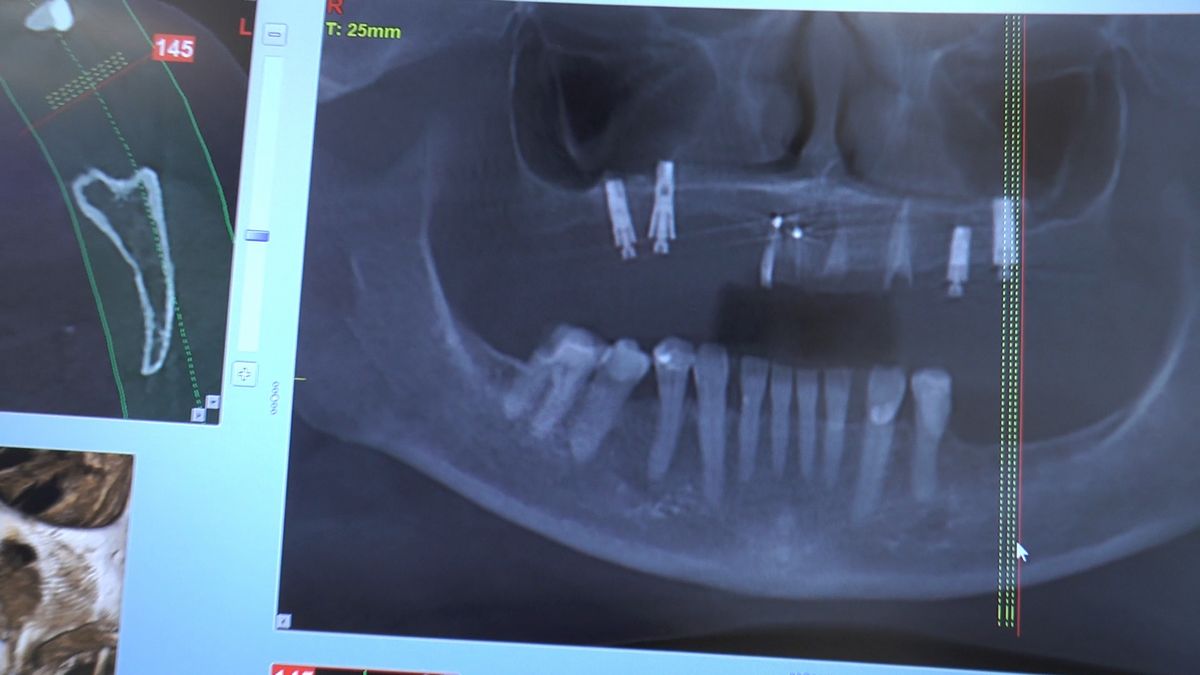

W ostatni weekend czerwca 2018 roku kursanci II Sezonu Preludium Implantologii odbyli piątą, finałową sesję, która w całości podporządkowana była praktyce. W ciągu dwóch dni zabiegowych Lekarze uczestniczący w szkoleniu przeprowadzili szereg zabiegów pod kierunkiem dr n.med. Violetty Szycik. Wszczepili 17 implantów oraz przeprowadzili ekstrakcje i zabiegi regeneracyjne kości. Zabiegi były wykonywane także w sedacji dożylnej z udziałem specjalisty anestezjologii i intensywnej terapii dr Jolanty Grzybowskiej. Preludium implantologii to nowy program edukacyjny dla adeptów implantologii stomatologicznej, którego celem jest wprowadzenie do implantologii poprzez pozyskanie wiedzy w szerokim zakresie i uwzględnieniem szczegółów mających decydujące znaczenie dla powodzenia leczenia implantologicznego. Ale tak jak wszystkie szkolenia w Instytucie Vivadental, w tym wiodące Practiculum Implantologii, zorientowane jest na praktyce i samodzielnym wykonywaniu zabiegów pod kierunkiem Mentora. To najlepsza edukacja w medycynie zabiegowej, a zarazem najlepszy start do implantologii.